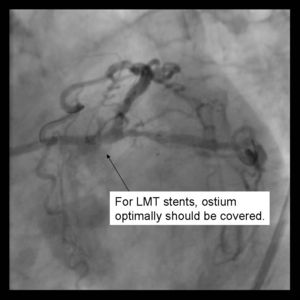

Requires minimum of a 8Fr Guiding system Optimal angle of bifurcation less than 90 degrees.

4) Using 2 Insufflators, both stents are inflated to low pressure. Then alternating with side branch and parent branch inflated to optimal deployment size. There is some risk of

over sizing the main branch with the overlapping stent segments. In the case where proximal disease may interfere with the 2 overlapping stents, a proximal stent may be

deployed prior to inflating the 2 distal stents. (Pants-and-trousers technique)